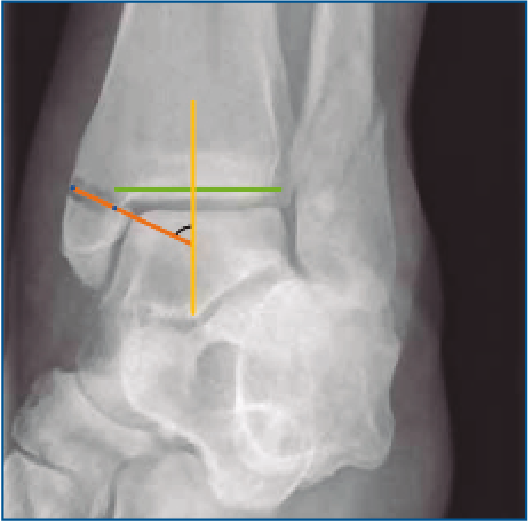

De cada uno, se han obtenido las siguientes mediciones radiológicas: tipo de lesión según Lauge-Hansen, número de maléolos afectados, medida del ángulo talocrural, ratio tibiofibular anteroposterior (AP), presencia o ausencia de superposición de colículos del maléolo interno con el peroneo, ECTF, solapamiento tibiofibular, ángulo de inclinación astragalina, línea de Shenton continua o discontinua, espacio claro medial y ángulo principal a estudio, el ángulo crurofocal medial (ACFM). Para analizar el ángulo principal, se debe obtener una línea perpendicular a la superficie articular tibial (del mismo modo que para el primer paso de la medición del ángulo talocrural); una vez hecho esto, se traza una línea entre el punto más medial y más lateral del trazo de fractura del maléolo interno en el origen tibial. El ACFM es el formado por esta línea y la perpendicular a la superficie articular tibial, y estará comprendido en un arco de valores posibles entre 0 y 180° (Figuras 1 y 2).

Figura 1. Representación esquemática de la medición del ángulo principal a estudio.